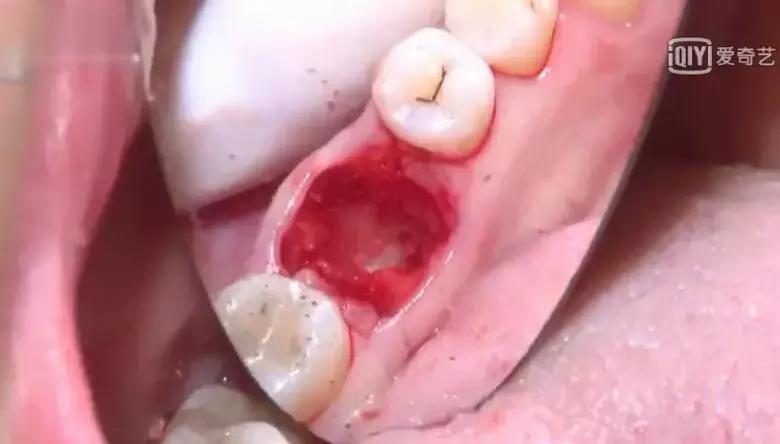

牙齿撬出来或者夹出来之后,就剩下空空的牙洞了,跟拔完树的树洞一样。

➤ Step 9 清创

医生为你清理伤口。医生给病人放在口腔拔牙创口上的纱布卷或棉花球,40分钟后吐出。

咬纱布卷的作用,一是压迫止血;二是隔离口水,使创口内的血凝结起来,有利于创口的早期愈合。